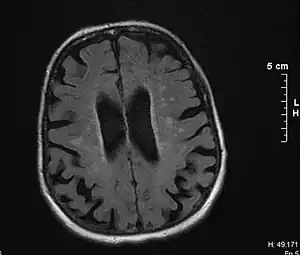

O diagnóstico de DV é feito com base no quadro clínico e em exames complementares de neuroimagem, podendo ser auxiliado pelo emprego de escalas específicas (como a escala de Hachinski e a escala Rose por exemplo). Seus principais diagnósticos diferenciais são outras demências porém existem evidências que indicam a possibilidade dela ocorrer simultaneamente ao Alzheimer.[7]